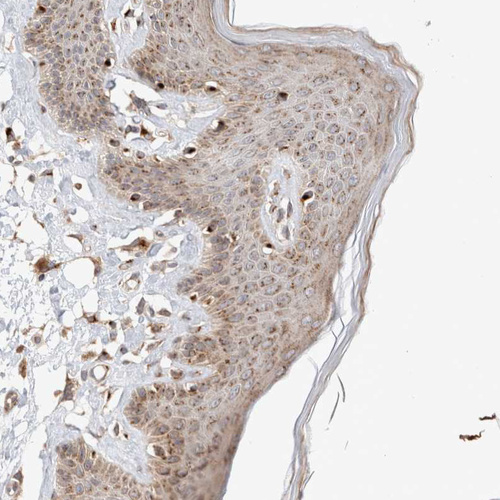

Immunohistochemical staining of human skeletal muscle, skin, stomach and testis using Anti-GCN1 antibody HPA024367 (A) shows similar protein distribution across tissues to independent antibody HPA018799 (B).